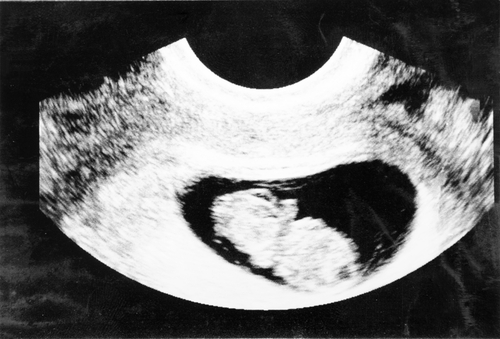

しっかり確認できたとこでようやく受診しました。すると赤ちゃんらしき影もしっかり見えてお医者さんからの「赤ちゃんいますね。元気ですよ」の言葉に涙が出ました。